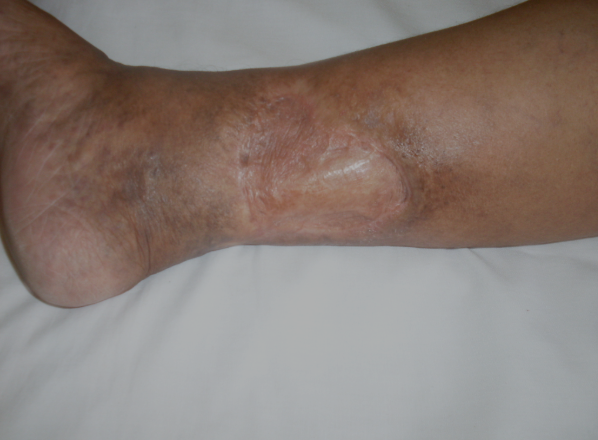

ÚLCERA VARICOSA - caso 09

Evolução Clínica

Giro de resultados antes e depois deste tratamento específico.